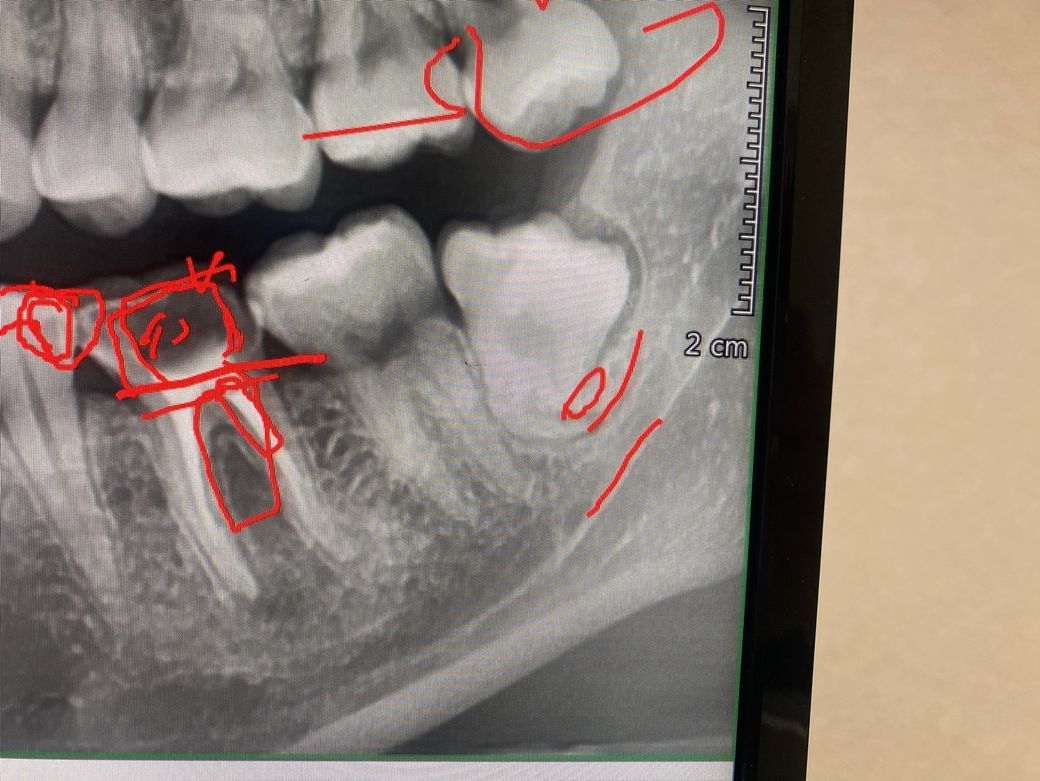

크라운 떨어져서 첫 내원했을때 찍은건데 이거보시면서 신경치료 잘되어있고 크라운만 다시 만들면 되겠다고 했는데

사진상으로 보면 신경치료 받은 치아 뿌리끝에 염증이 잇어 보입니다. 뿌리끝에 보면 동그랗게 뭔가 잇어 보이는데 이건 염증인거 같습니다.

현재 사진에서는 염증이 있습니다. 다만 신경치료를 하고 나서도 해당 사진에서는 염증이 있는 것처럼 보이며 추적관찰을 하면서 염증이 서서히 사라질 수도 있습니다. 따라서 단편적인 사진 하나만으로는 판단이 어렵습니다.

사진으로 염증이 보입니다. 치근단 농양일 것으로 보입니다.

사진과 같이 염증이 보이는 경우, 크라운을 다시할 경우 재신경치료를 먼저 하고 크라운을 다시할지 판단해야합니다.

염증이 있더라도, 크기가 크지 않고 경미하고, 증상이 전혀 없다면 재신경치료하지 않고 그냥 크라운만 하는 경우도 있습니다. 물론 미리 재신경치료의 가능성을 고지하는게 바람직합니다.

만약 염증이 크고, 증상이 있는 상태라면, 크라운하기 전에 재신경치료를 하거나, 재신경치료를 해도 효과가 크지 않다고 판단된다면 발치쪽으로 가는경우도 있습니다.